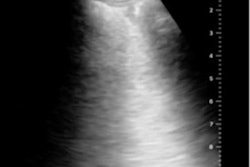

The three male patients in the study were all admitted to a hospital in Italy with laboratory-confirmed COVID-19 and pneumonia-like symptoms. However, when doctors performed contrast-enhanced ultrasound scans on the patients, they found large perfusion defects in a pattern not typical of pneumonia or lung collapse.

The three patients in the study all underwent radiographic and chest ultrasound examinations within three hours of admission. The ultrasound findings were as expected for patients with COVID-19, including B-lines that were often grouped and confluent in areas of white lung.

However, the three patients also had echographic parenchymal consolidations at the bases and more than one nonbasal subpleural consolidation, less than 2 cm in diameter, with a wedge-shaped or angular appearance.

The subpleural consolidations, combined with high D-dimer values and the inability to perform chest CT, led the doctors to perform contrast-enhanced ultrasound scans. Notable findings included the following:

- Abnormal early arterial enhancement in the first nine seconds following administration. The effect was partial in nature, often not uniform, and displayed no evidence of pulmonary arteries in a segmentary arrangement.

- Incomplete enhancement of major consolidations, especially in the pulmonary cortex.

- Sharp boundaries between perfused and nonperfused areas.

- No enhancement of consolidations less than 2 cm. Instead, the consolidations behaved as ischemic or infarct regions.